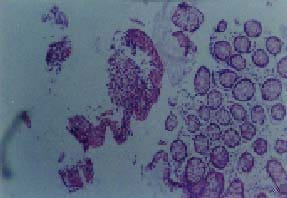

Múltiples, de 2 a 3 cm de diámetro, con fondo recubierto de fibrina entre áreas respetadas de mucosa normal en colon transverso, descendente y sigmoide. En el ciego, se observó una extensa lesión de iguales características que rodeaba la válvula ileocecal (figura 1), obstruyéndola parcialmente; la progresión del colonoscopio al íleon mostró compromiso similar en los últimos diez cm del íleon distal (figura 2), que adoptó una morfología tubular. Se tomaron múltiples biopsias en las que se observó un epitelio colónico ulcerado (figura 3) con áreas aisladas de necrosis (figura 4) que mostraron la presencia de gran cantidad de microconidias (figura 5) y que fueron confirmadas como correspondientes a HC.

Figura 3. Epitelio colónico ulcerado. Hematoxilina-eosina, 10X.

Figura 4. Area necrótica de la mucosa con sospecha de microorganismos. Hematoxilina-eosina, 40X.